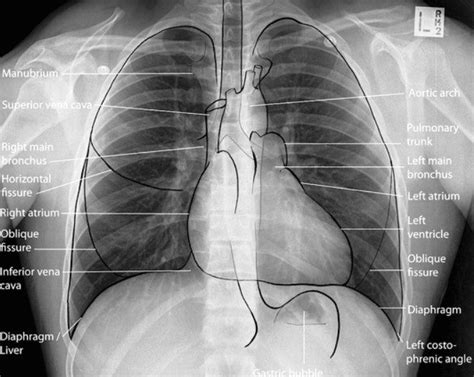

When an X-ray beam is directed at your body, different tissues absorb the radiation to varying degrees. Dense materials, like bone, which are packed tightly together, absorb more X-rays. Softer tissues, like muscles and organs, absorb fewer X-rays. The X-rays that aren’t absorbed pass through to a detector on the other side, usually a digital sensor or photographic film. This creates a radiograph , which is essentially a shadow picture. Bones appear white or light gray because they block the X-rays, while air-filled areas, like your lungs, appear black because the X-rays pass through them easily. Everything else falls somewhere in between, giving us a detailed, albeit grayscale, image of your internal structures. It’s this difference in absorption that allows doctors to see things like fractures, infections, or even foreign objects inside you without having to cut you open. Pretty neat, huh?